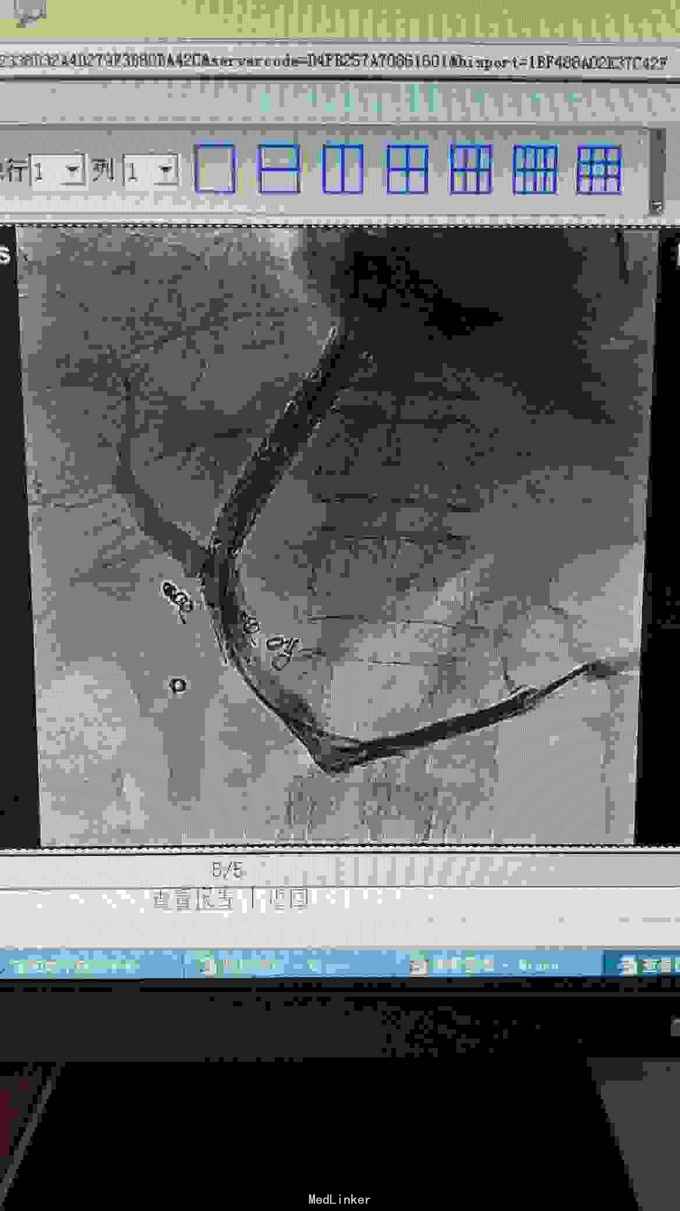

TIPS术后限流性支架植入

72女性,乙肝肝硬化门静脉高压合并肝动脉门静脉瘘,外院行肝动静脉瘘栓塞,术后出现消化道出血、顽固性腹水、门静脉血栓,转我院后给予性TIPS,术后12小时转氨酶快速升高,考虑分流过度、肝衰,24小时内行限流术,术后48小时转氨酶明显降低,术后7天安全出院。